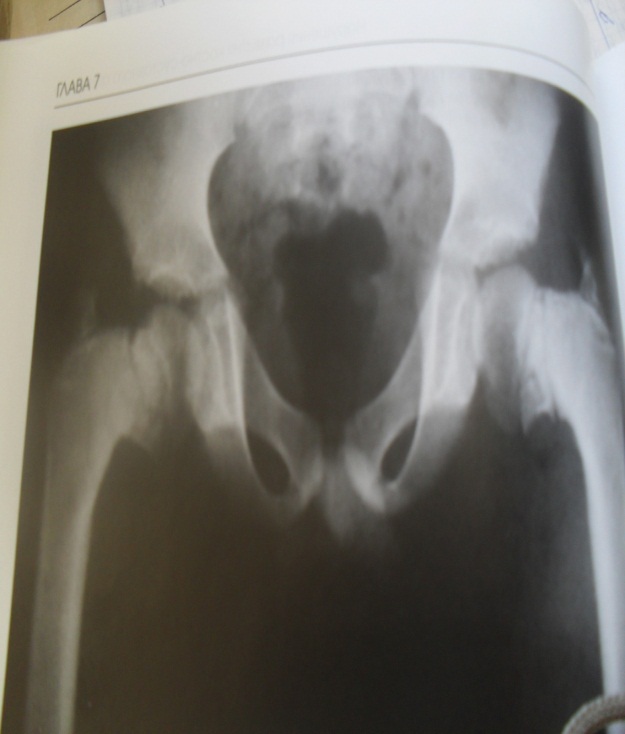

Рентгенологическая картина какого заболевания представлена на рентгенограмме© +вывих левого бедра© Болезнь Пертеса© Эпифизарный остеомиелит© Перелом шейки бедра© Остеомиелит седалищной кости

***

Для какого заболевания характерна рентгенограмма© остеомиелит головок бедренных костей© вывих головки левого бедра© болезнь Пертеса© +диспластический коксартроз© остеомиелит седалищной кости

Для какого заболевания характерна рентгенкартина© Метафизарная дисплазия© Болезнь Пертеса© +Двусторонний коксартроз© Остеомиелит головки бедренной кости© Эпифизарная дисплазия

Что вы видите на рентгенограмме© дисплазия тазобедренного сустава© +врожденный вывих бедра© болезнь Пертеса© остеомиелит головки бедренной кости© болезнь Осгуд-Шлаттера

Какому состоянию соответствует рентгенкартина© Вальгусная деформация© Дисплазия тазобедренных суставов© +Варусная деформация© Диспластический коксартроз© Остеомиелит Гарре

Консультация какого специалиста необходима в этом случае© Нервопатолога© Педиатра© Онколога© Неонатолога© +ортопеда